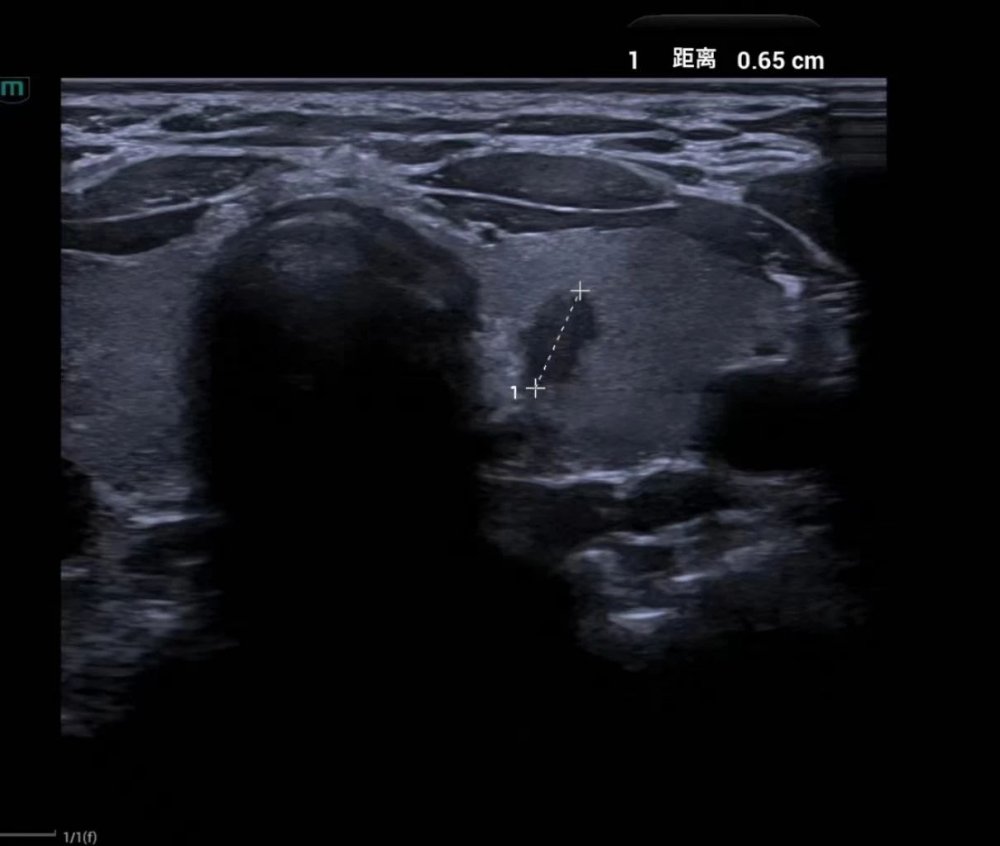

9月上旬,32岁的李女士在医院体检时发现甲状腺左叶多发结节。李女士比较担忧,想进一步辨别结节的良恶性,医学超声科立即为她安排了超声引导下甲状腺结节细针穿刺活检术(FNA)。经超声引导,穿刺针精准进入病灶并取得了满意的标本。操作时间仅10分钟,整个术程顺利,李女士也没有感觉到不适。术后经医院病理科诊断,李女士的甲状腺结节的病理结果为可疑甲状腺乳头状癌。考虑瘤体较小,医生建议李女士先行观察,定期随诊,李女士这才放下心来。